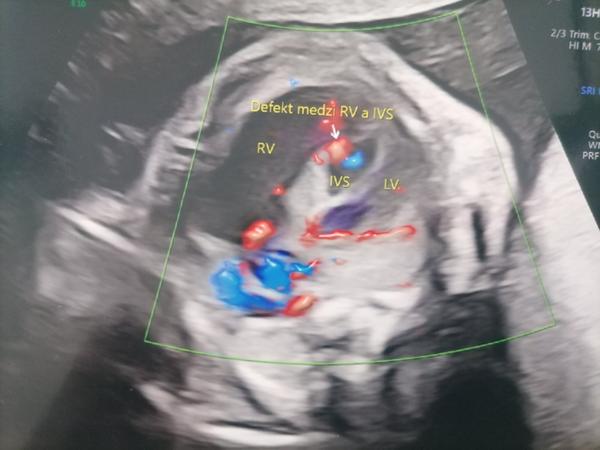

popísaný nález nie je typickým obrazom pre vrodenú chybu srdca u detí.

Doporučujem Vám objednať sa na kontrolné prenatálne vyšetrenie v Detskom kardiocentre ešte pred narodením dieťaťa s cieľom potvrdenia uvedenej diagnózy.